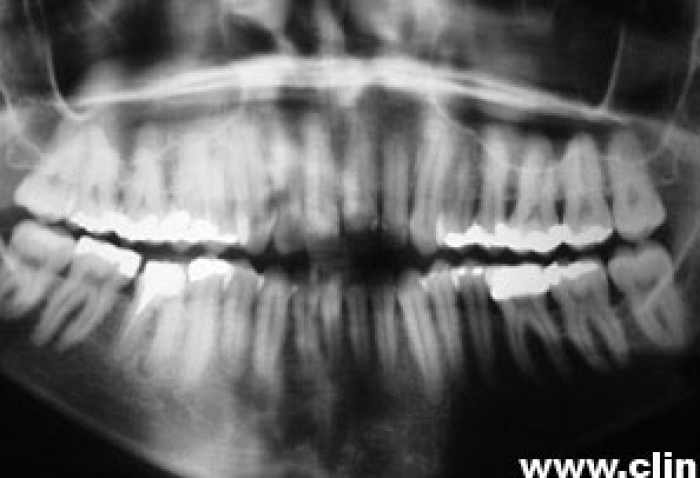

Raio X inicial